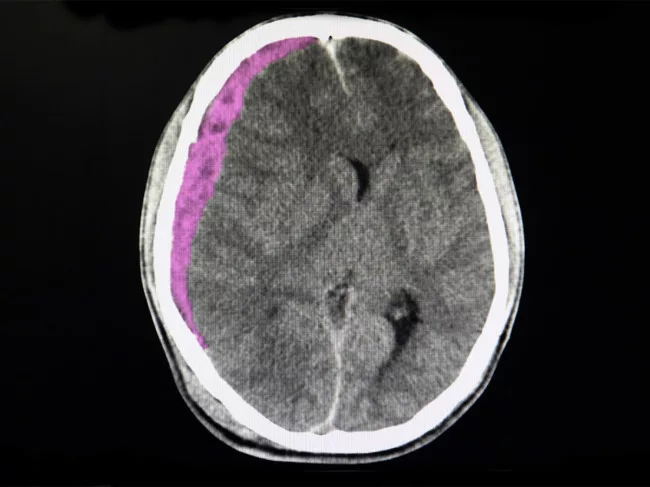

CT scan of brain showing subdural hematoma

FDA greenlights Medtronic Onyx subdural hematoma treatment

Sometimes the darkest products (names) bring a bright spot of news to their developers, as the U.S. FDA clearance for Galway, Ireland-based Medtronic plc's Onyx liquid embolic system demonstrates. Onyx gained the indication for embolization of the middle meningeal artery as an adjunct to surgery for the treatment of symptomatic subacute or chronic subdural hematoma based on the EMBOLISE trial results. The approval represents a significant advancement in treating this common neurosurgical condition. Read More